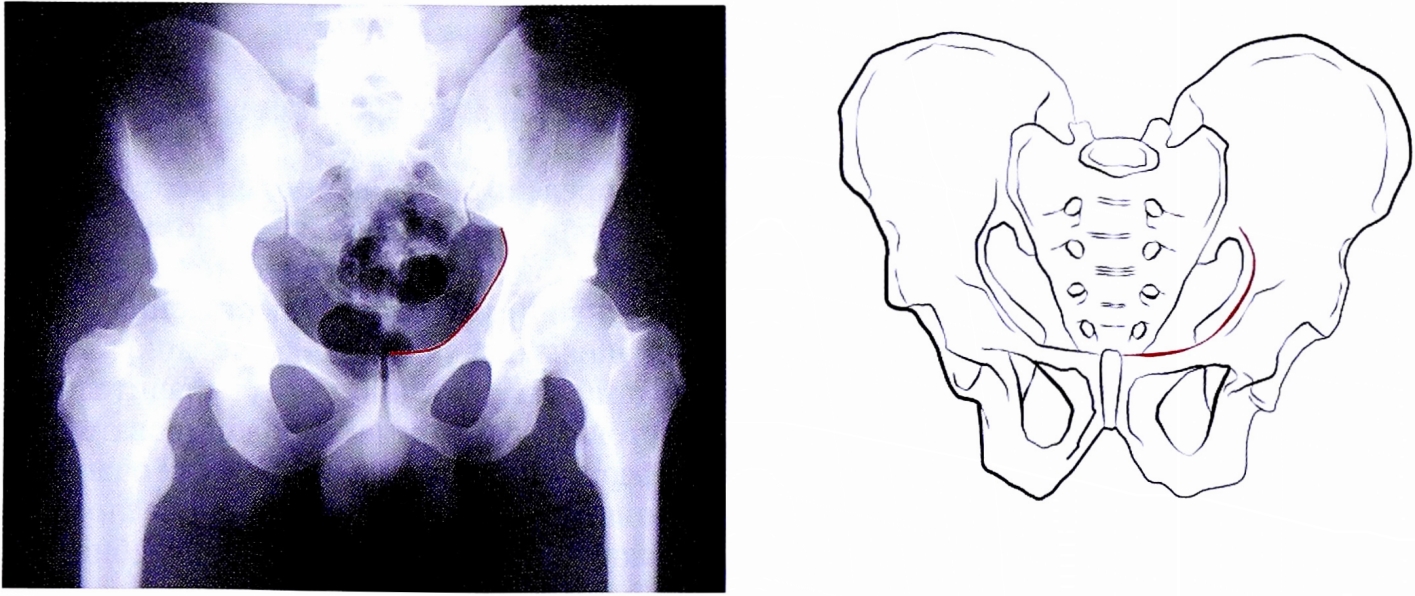

- Подвздошно-седалищная линия образована наложением внутреннего и наружного кортикального слоя четырехсторонней пластины. Рентгенологическая тень соответствует анатомическим контурам внутренней поверхности четырехсторонней пластинки и медиальной поверхности нисходящей ветви седалищной кости, в верхних отделах она соответствует контурам большой седалищной вырезки, представляет внутритазовую поверхность задней колонны и дна вертлужной впадины (рис. 2).

Рис. 2. Подвздошно-седалищная линия на рентгенограмме и на схематическом изображении таза.

Fig. 2. Ileoischial line on AP pelvic X-ray and on schematic pelvis.